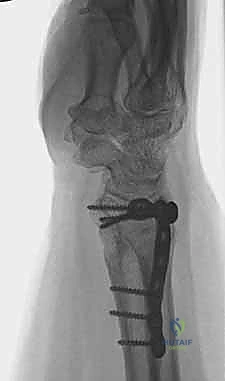

ثانياً: العلاج الجراحي (Surgical Intervention)

متى يقرر الدكتور هطيف ضرورة التدخل الجراحي؟

1. عدم الاستقرار (Instability): إذا كان المفصل الزندي الكعبري البعيد (DRUJ) غير مستقر بعد تثبيت كسر الكعبرة.

2. الانزياح (Displacement): إذا كان الكسر في قاعدة الناتئ الإبري منزاحًا بأكثر من 2 ملم.

3. الكسور المفصلية: أي كسر يخل بتطابق السطح المفصلي لرأس الزند.

4. الكسور المفتتة: في الجزء الكردوسي التي تؤدي إلى قصر عظم الزند.

التخطيط الجراحي لكسور الزند

وجه المقارنة العلاج التحفظي (الجبس/الجبيرة) العلاج الجراحي (تثبيت داخلي بصفائح ومسامير)

دواعي الاستخدام الكسور المستقرة، غير المنزاحة، كسور قمة الناتئ الإبري. الكسور المفتتة، المنزاحة، الكسور المفصلية، عدم استقرار DRUJ.

مدة التثبيت الأولية 4 إلى 6 أسابيع من التثبيت الكامل. بدء الحركة المبكرة (أحيانًا بعد أيام قليلة من الجراحة).

المزايا تجنب مخاطر الجراحة والتخدير، تكلفة أقل. استعادة التشريح الدقيق، حركة مبكرة، منع تيبس المفاصل، استقرار فوري.

العيوب والمخاطر احتمالية تيبس المعصم، ضعف العضلات، خطر عدم الالتئام أو الالتحام المعيب. مخاطر التخدير، احتمالية العدوى، الحاجة لجراحة مستقبلية لإزالة الصفائح (نادرًا).

التأهيل الوظيفي يتأخر حتى إزالة الجبس. يبدأ مبكرًا جدًا مما يعطي نتائج وظيفية أفضل وأسرع.

صورة توضح الفرق بين التثبيت الداخلي والجبس

خطوات التدخل الجراحي الدقيق مع الأستاذ الدكتور محمد هطيف

تُعد جراحات المعصم والزند من الجراحات الدقيقة التي تتطلب مهارة عالية، وهو المجال الذي يتفوق فيه الأستاذ الدكتور محمد هطيف بفضل استخدامه لتقنيات الجراحة المجهرية (Microsurgery) والأدوات الجراحية ذات التقنية العالية.

1. التخطيط ما قبل الجراحة (Pre-operative Planning)

يقوم الدكتور هطيف بدراسة الأشعة المقطعية ثلاثية الأبعاد بدقة، ويختار نوع وحجم الصفائح المعدنية (Plates) والمسامير (Screws) المناسبة لكل مريض بناءً على حجم العظم ونوع الكسر.